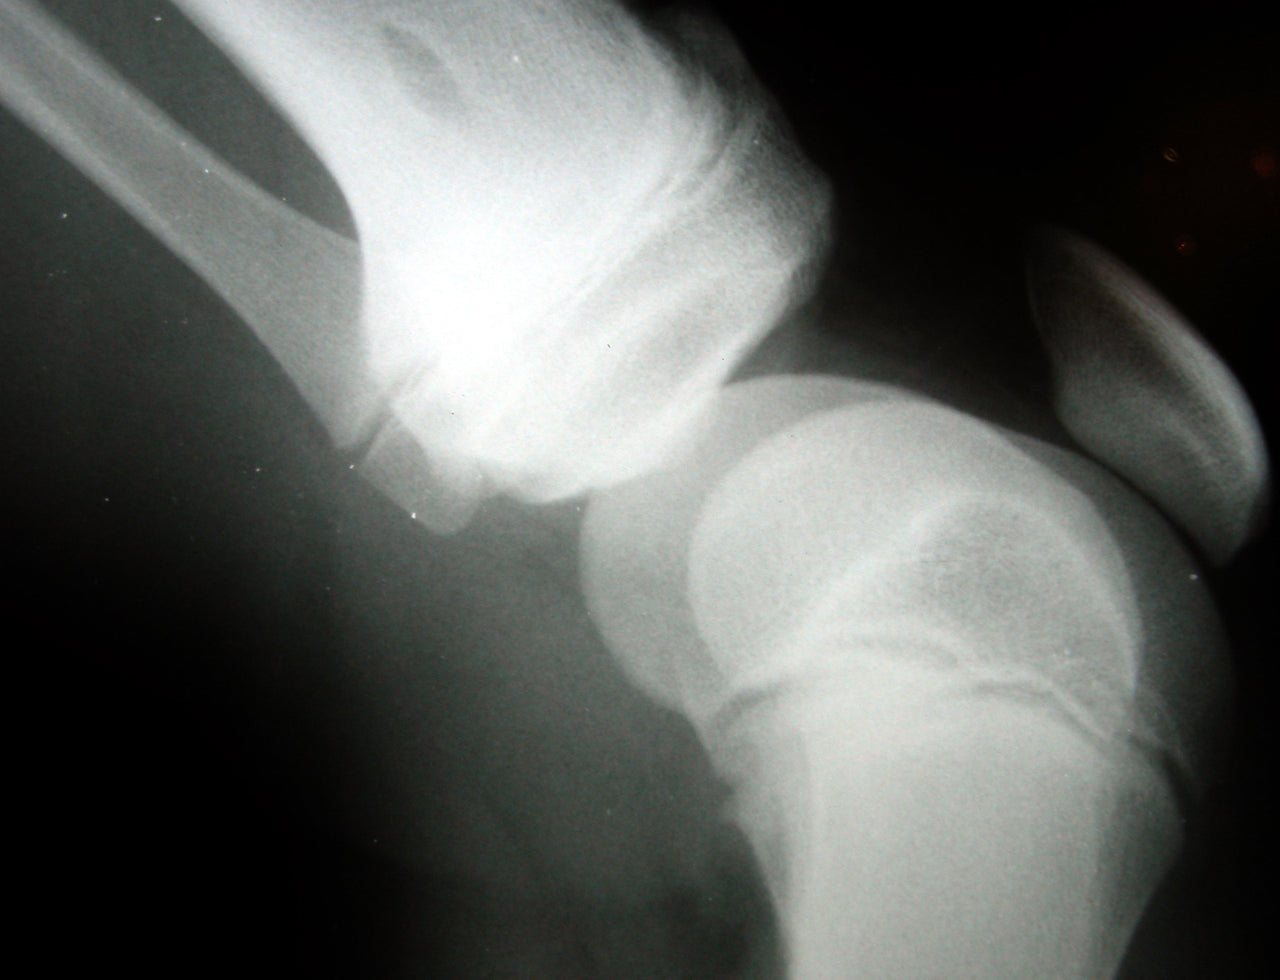

Le artriti sono un insieme di condizioni diverse che hanno in comune la caratteristica di provocare infiammazione a livello articolare, gonfiori, irrigidimento, e dolori che portano ad una perdita di funzionalità dell’articolazione. La prevalenza dell’ artrite del ginocchio è in aumento con l' invecchiamento della popolazione ed è aggravata dal crescente numero di obesi e anziani. Diversi studi negli ultimi anni hanno suggerito che la carenza di vitamina D negli adulti può aggravare osteopenia, osteoporosi, debolezza muscolare, fratture, malattie autoimmuni, malattie infettive e cardiovascolari. Bassi livelli di vitamina D misurati nel siero come 25-idrossivitamina D (25 (OH) D), in anziani e obesi, sono correlati con diverse condizioni di salute compreso il dolore cronico.

Il dottor Glover, che ha diretto lo studio, e i suoi colleghi hanno raccolto e analizzato i dati provenienti da 256 persone con un' età media di 57 anni. I partecipanti hanno fornito un report riguardante il dolore da osteoartrite del ginocchio e sono stati sottoposti a un test delle prestazioni funzionali degli arti inferiori. Livelli di vitamina D sono stati ottenuti analizzando i campioni di sangue di ogni soggetto. I risultati hanno mostrato che nelle persone obese ma con adeguati livelli di vitamina D, il dolore al ginocchio era minore rispetto a quello di obesi e con carenza della vitamina. Inoltre, anche alcune prestazione motorie come ad esempio alzarsi in piedi da una posizione seduta, sembravano significativamente migliori in coloro con maggiori concentrazioni di vitamina D nel sangue.